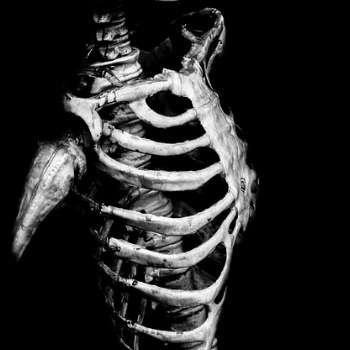

골다공증 증상 1. 뼈의 취약성 증가

골다공증의 가장 중요한 특징 중 하나는 뼈의 취약성이 크게 증가한다는 점입니다. 뼈가 약해져서 작은 충격이나 일상적인 활동에서도 쉽게 골절이 발생할 수 있습니다. 특히 척추, 고관절, 손목 등의 부위에서 골절이 자주 발생하며, 이러한 골절은 심각한 통증과 기능 장애를 초래할 수 있습니다. 예를 들어, 갑작스러운 낙상이나 가벼운 부딪힘으로 인해 손목 골절이나 고관절 골절이 발생할 수 있으며, 이는 환자의 일상생활에 큰 영향을 미칩니다.